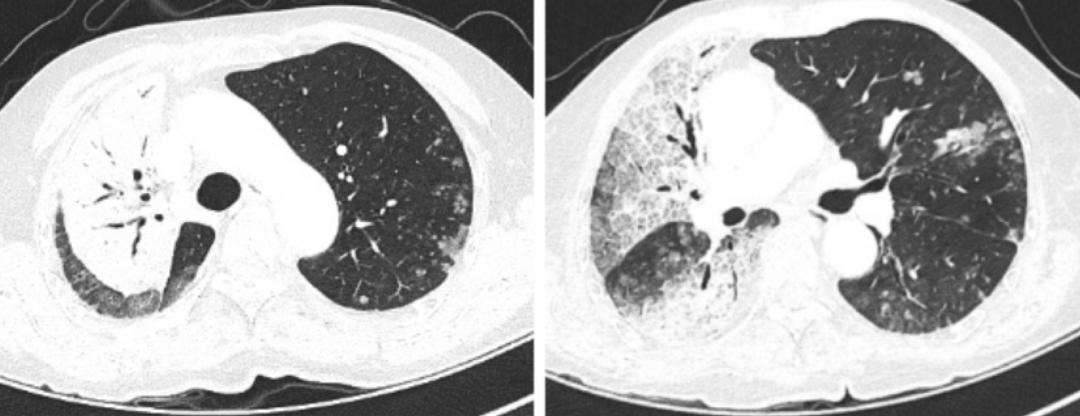

对其辅助检查的情况为:ESR 24mm/h,超敏C反应蛋白10.6mg/l,血常规、降钙素原、凝血、内毒素、真菌D-葡聚糖、半乳甘露聚糖肽、支原体、衣原体、嗜肺军团菌抗体、肝肾功、电解质、心肌酶、电解质均正常;结核感染T淋巴细胞检测阳性,结核杆菌抗体、结核杆菌DNA、PPD试验阴性;自身抗体、抗中性粒细胞抗体、风湿系列阴性;肿瘤标志物NSE 18.25 ng/ml(正常值0—16.3ng/ml);血气分析(FiO2 21.0%)示pH 457、pO2 59.9mmHg、pCO2 31.7mmHg、SaO2 92.0%。以下为该患2019年5月22日胸部CT的影像学资料:

胸部CT提示两肺可见片状密度增高影,以右肺为主,其内可见支气管充气征,两肺斑片状磨玻璃及稍高密度影,并纤细网格状影,呈铺路石改变。

2019年5月22日:

2019年11月11日: